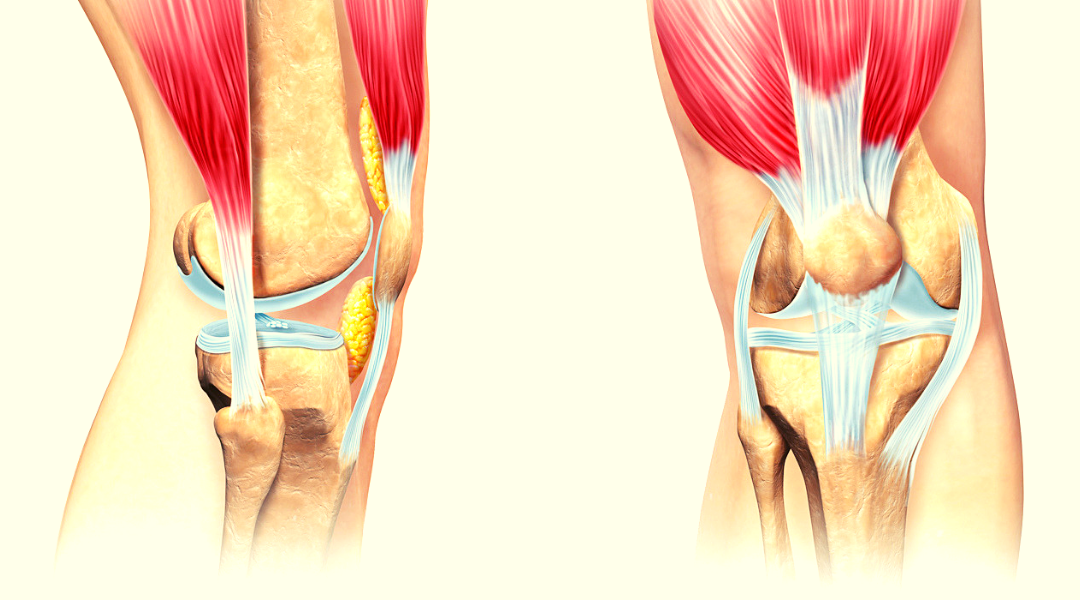

Проблемы с коленным суставом: флоттация и лечение